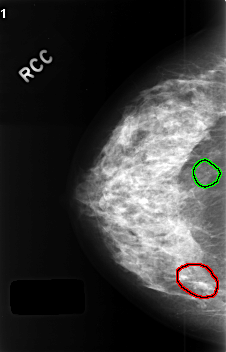

FILE: C_0407_1.RIGHT_CC.OVERLAY

TOTAL_ABNORMALITIES 2

ABNORMALITY 1

LESION_TYPE CALCIFICATION TYPE AMORPHOUS DISTRIBUTION CLUSTERED

ASSESSMENT 4

SUBTLETY 3

PATHOLOGY BENIGN

TOTAL_OUTLINES 1

BOUNDARY

ABNORMALITY 2

LESION_TYPE CALCIFICATION TYPE PLEOMORPHIC DISTRIBUTION SEGMENTAL

ASSESSMENT 3